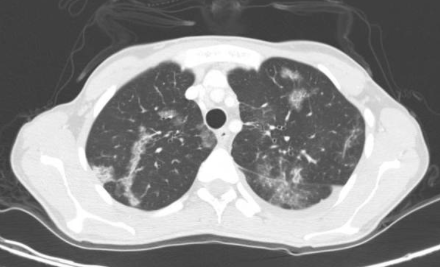

Crazy paving differentials

1. Pulmonary alveolar proteinosis (filling of alveolar spaces with protein)